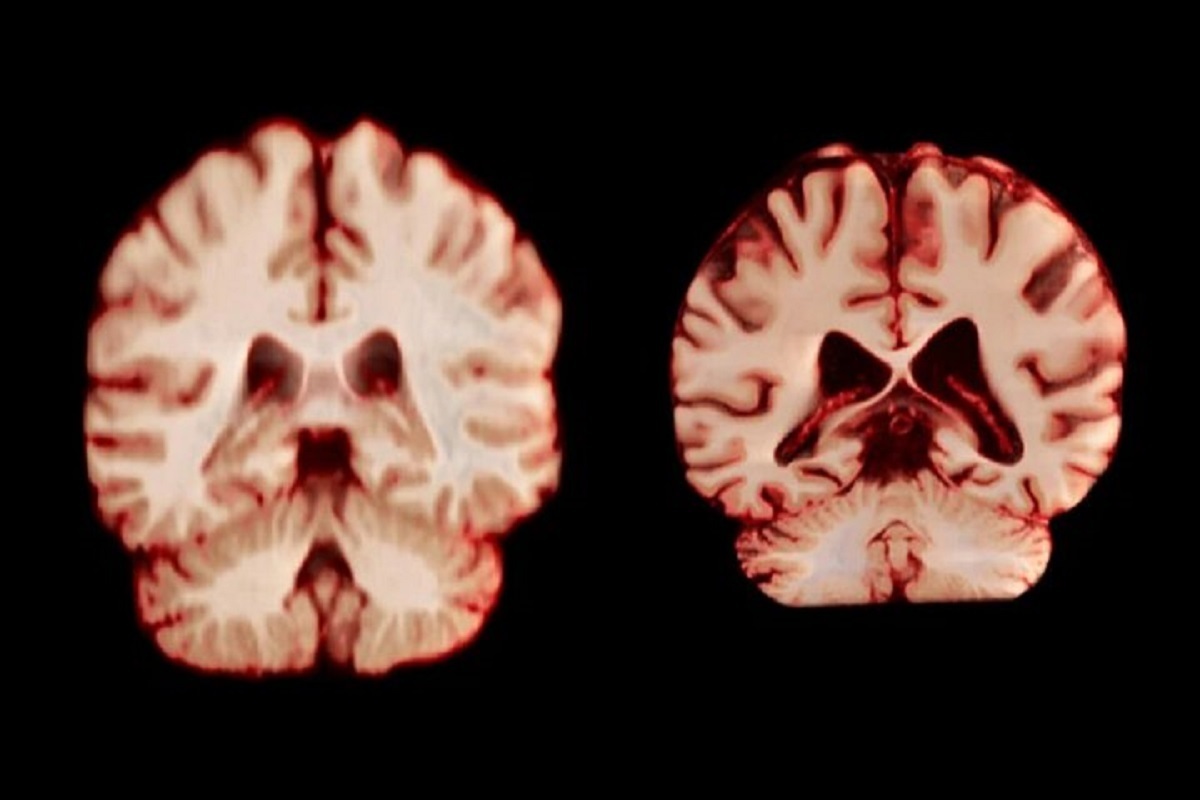

اسکن مغز

جدیدترین مطالعه شامل بیش از ۱۲ هزار و ۵۰۰ اسکن مغزی تصویربرداری تشدید مغناطیسی (MRI) از ۴۷۲۶ نفر بود که حداقل دو اسکن برای هر نفر، با فاصله متوسط سه سال انجام شده بود که به بیماری آلزایمر یا هرگونه اختلال شناختی مبتلا نبودند و به عنوان شرکتکننده کنترل در ۱۴ مجموعه داده بزرگتر قرار داشتند. محققان با بررسی عواملی از جمله ضخامت ماده خاکستری و اندازه نواحی مرتبط با بیماری آلزایمر، مانند هیپوکامپ که برای حافظه ضروری است، نحوه تغییر ساختار مغز افراد را در طول زمان مقایسه کردند.

به طور کلی، مردان در مقایسه با زنان، کاهش حجم بیشتری را در مناطق بیشتری از مغز تجربه کردند. به عنوان مثال، قشر پس مرکزی که مسئول پردازش احساسات لامسه، درد و دما و همچنین موقعیت و حرکات بدن است، در مردان سالانه ۲.۰ درصد و در زنان سالانه ۱.۲ درصد کاهش یافت.